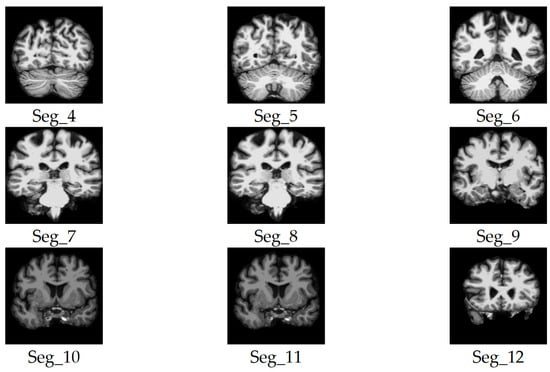

3.3. Automated 2D Slice Selection